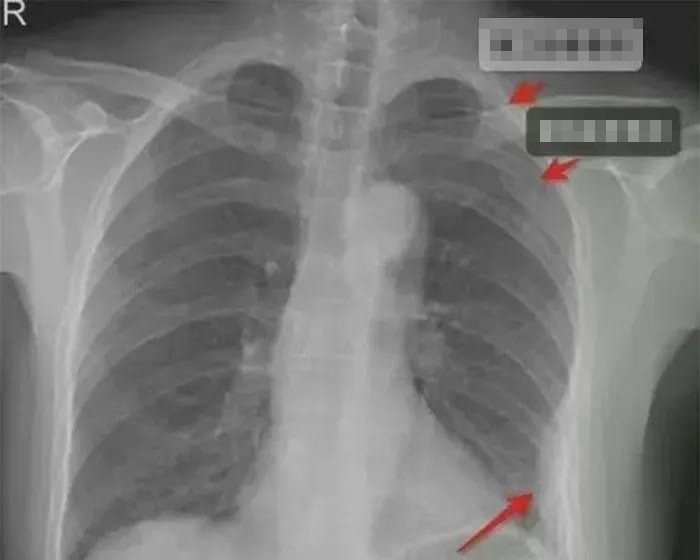

| Phim chụp cho thấy, cô bị gãy 2 xương sườn trước bên phải và 1 xương sườn bên trái. |